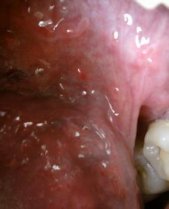

尖锐湿疣    尖锐湿疣(condyloma acuminatum)又称又称尖圭湿疣,生殖器疣或性病疣,是由人类乳头瘤病毒(human papilloma virus,HPV)感染引起的好发于外阴及肛门的性传播疾病;HPV有多种类型,引起本病的主要类型为HPV1、2、6,11、16、18,31、33及35型等,而尖锐湿疣

尖锐湿疣是怎么引起的?该怎

尖锐湿疣 是一种常见的性传播疾病之一,尖锐湿疣的传……[详细]